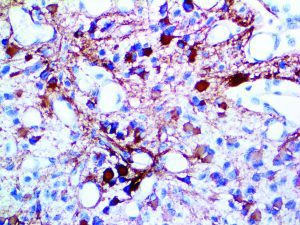

This activation induces inflammatory monocytes to highly express IL-6, starting a localized and then systemic cascade effect that results in hyperproduction of IL-6, which accelerates the inflammatory process. Because IL-6 also increases vascular permeability, excessive levels cause blood vessels to become very leaky. This, along with clotting factors released from vascular endothelial cells, stimulates the coagulation cascade, resulting in microthrombosis (tiny clots), which leads to ischemia and tissue death of the kidney, intestines, heart, liver, brain and extremities.